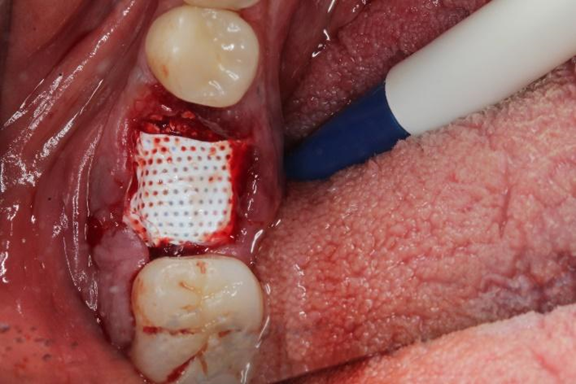

Uma paciente de 62 anos de idade apresentou-se com queixa de odor ruim na região do dente 46, pus, bolsa profunda e sangramento à sondagem. Os exames radiográficos evidenciaram lesão periapical, tratamento endodôntico e uma linha de fratura condenando a sobrevivência do elemento dentário 46. Assim, o elemento foi extraído e foi instalado um implante dentário de conexão interna morse no momento da exodontia. O mesmo foi estabilizado a 20Ncm e o parafuso de cobertura foi instalado. Em seguida, um biomaterial de origem bovina foi compactado no GAP e uma membrana não absorvível foi posicionada protegendo o biomaterial.

Após a análise clínica e tomográfica foi realizado o planejamento do caso: exodontia do dente 46 com a instalação imediata de um implante Cone Morse de corpo cônico (Maestro 4.0 X 9 – Implacil De Bortoli, São Paulo, Brasil), regeneração óssea guiada com biomaterial de origem bovina e colocação de uma barreira regenerativa não absorvível Cytoplast.